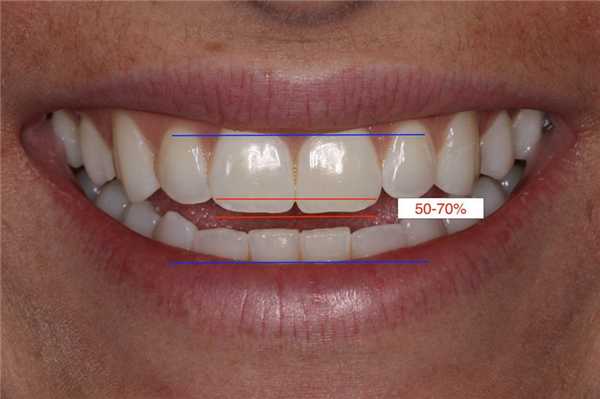

Получение данного фото является несколько затруднительным. Нужно попросить пациента облизать губы, затем глотнуть, а потом указать, чтобы он/она не ворошили губами, сохраняя состояние покоя. Фото при произношении звука "Э" используется для того, чтобы определить приблизительно необходимую длину режущего края, а также оценить потенциальную гиперподвижность верхней губы. При данном приеме определяют расстояние от линии верхней губы до линии нижней губы для того, чтобы спроектировать будущую позицию режущего края. В качестве ориентира можно использовать тот факт, что центральные резцы должны занимать от 50% до 70% пространства между линиями верхних и нижних губ (фото 4).

Фото 4. Фото при произношении звука «Э»: режущий край находится на 50-70% расстояния между линиями верхней и нижней губы.